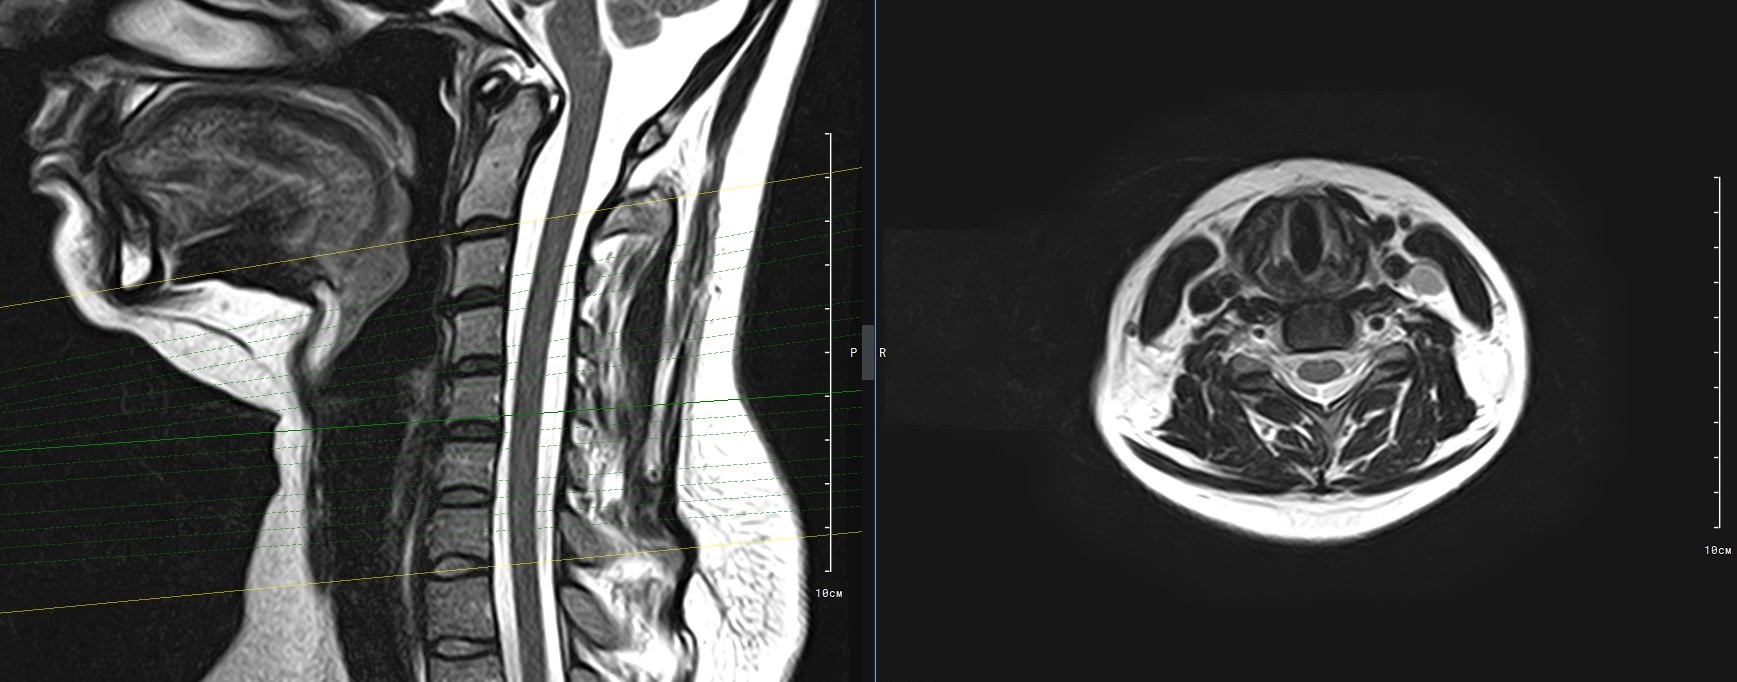

Для того, чтобы оценить состояние шейных позвонков с прилегающими тканями и одновременно визуализировать плечевой сустав, в нашей клинике выполняется комплексное обследование, включающее два протокола: МРТ шейного отдела позвоночника и МРТ плечевого сустава.

Метод МРТ позволяет оценить состояние всех анатомических областей шейного отдела позвоночника: костную структуру позвонков, спинной мозг с отходящими от него нервными корешками и окружающие мягкие ткани. Протокол обследования плечевого сустава включает оценку костной структуры, суставной капсулы, полости сустава с выстилающей его синовиальной оболочкой, связок, сухожилий, мышц и окружающих мягких тканей.